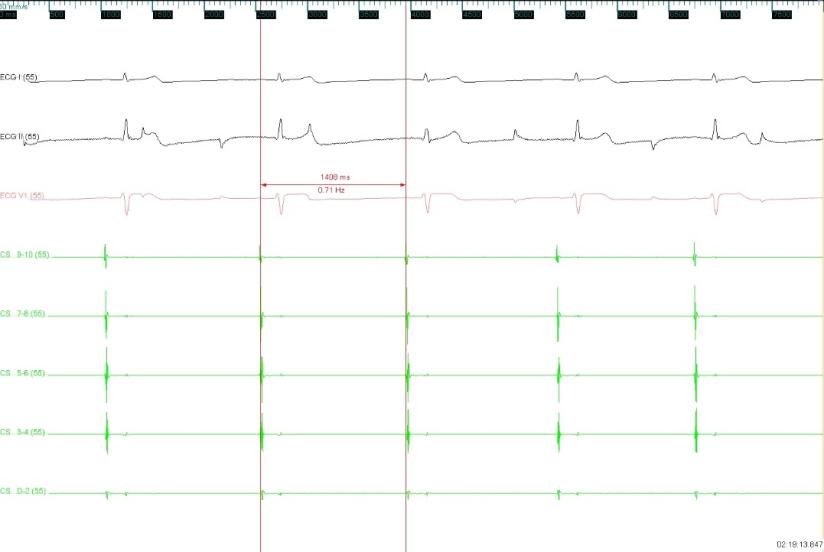

图2 消融右前GP时窦性心房频率增快,房室非1:1下传,心室率稍增快